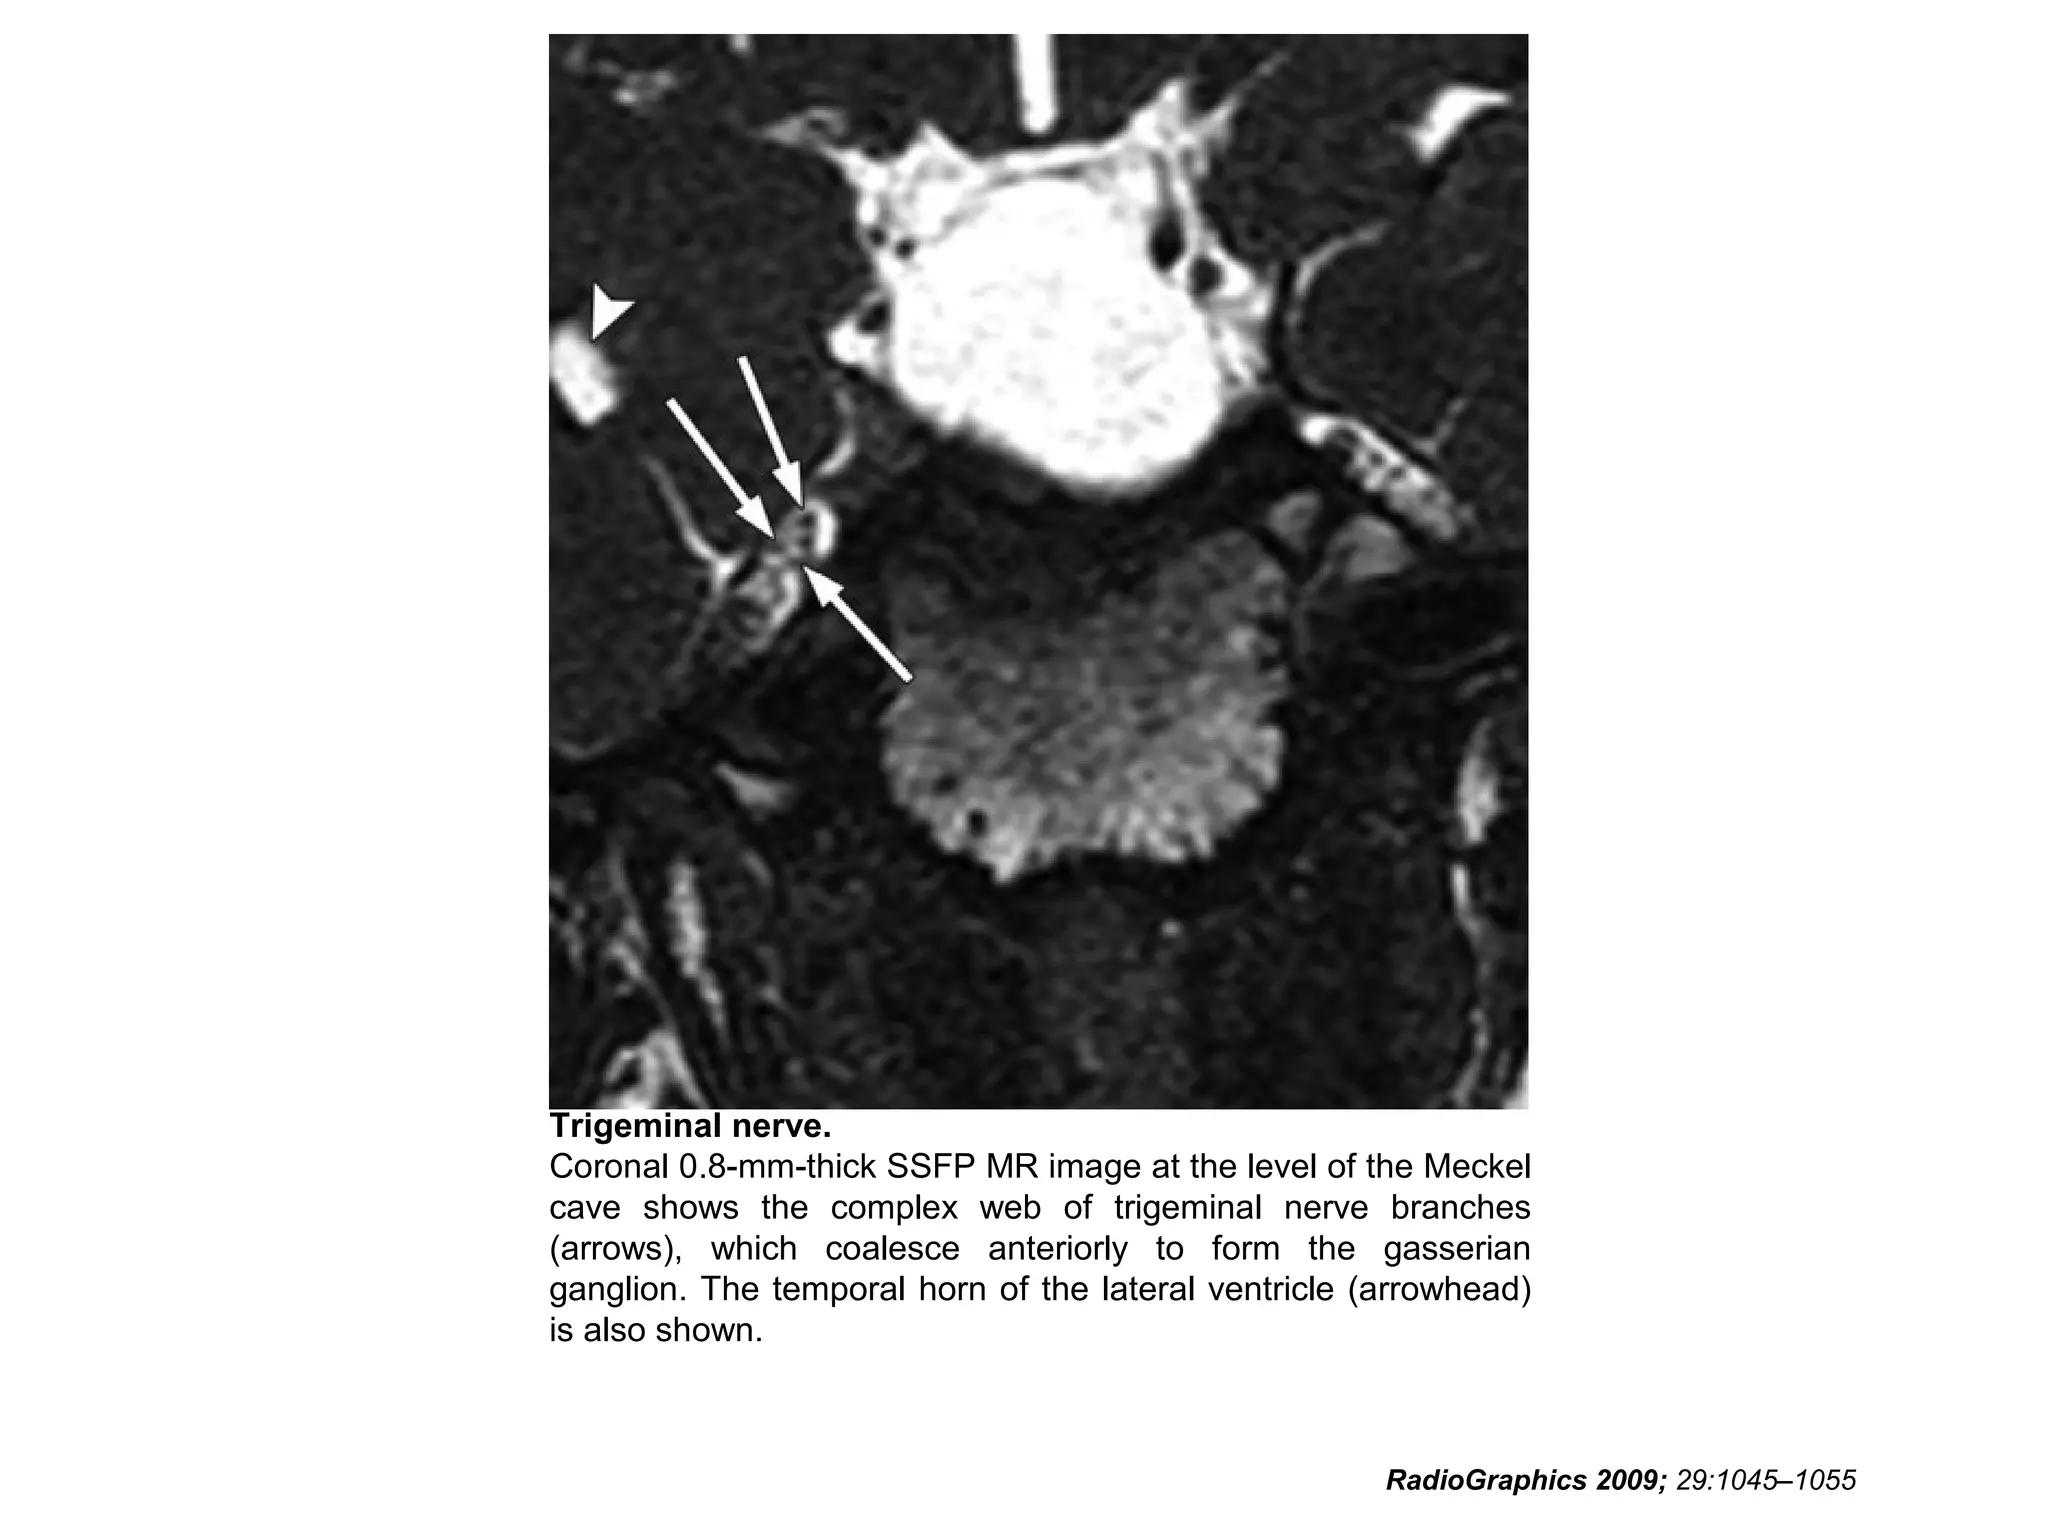

Trigeminal nerve.

Coronal 0.8-mm-thick SSFP MR image at the level of the Meckel

cave shows the complex web of trigeminal nerve branches

(arrows), which coalesce anteriorly to form the gasserian

ganglion. The temporal horn of the lateral ventricle (arrowhead)

is also shown.

RadioGraphics 2009; 29:1045–1055

Cranial Nerve V: TheTrigeminal Nerve • In the Meckel cave, the nerve forms a meshlike web that can be visualized only with high-resolution imaging. • Along the anterior aspect of the cavity, the trigeminal nerve forms the trigeminal (gasserian) ganglion before splitting into three subdivisions. • The ophthalmic (V1) and maxillary (V2) divisions of the nerve move medially into the cavernous sinus and exit the skull through the superior orbital fissure and foramen rotundum, respectively. • The mandibular division (V3), which includes the motor branches, exits the skull inferiorly through the foramen ovale. RadioGraphics 2009; 29:1045–1055

Trigeminal nerve. Coronal 0.8-mm-thickSSFP MR image at the level of the Meckel cave shows the complex web of trigeminal nerve branches (arrows), which coalesce anteriorly to form the gasserian ganglion. The temporal horn of the lateral ventricle (arrowhead) is also shown. RadioGraphics 2009; 29:1045–1055